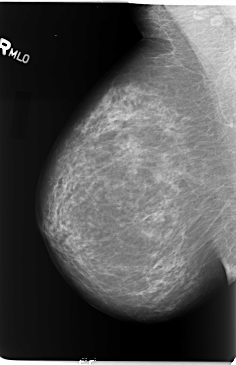

B_3110_1.LEFT_MLO

LEFT_MLO LINES 5832 PIXELS_PER_LINE 3896 BITS_PER_PIXEL 12 RESOLUTION 50 OVERLAY